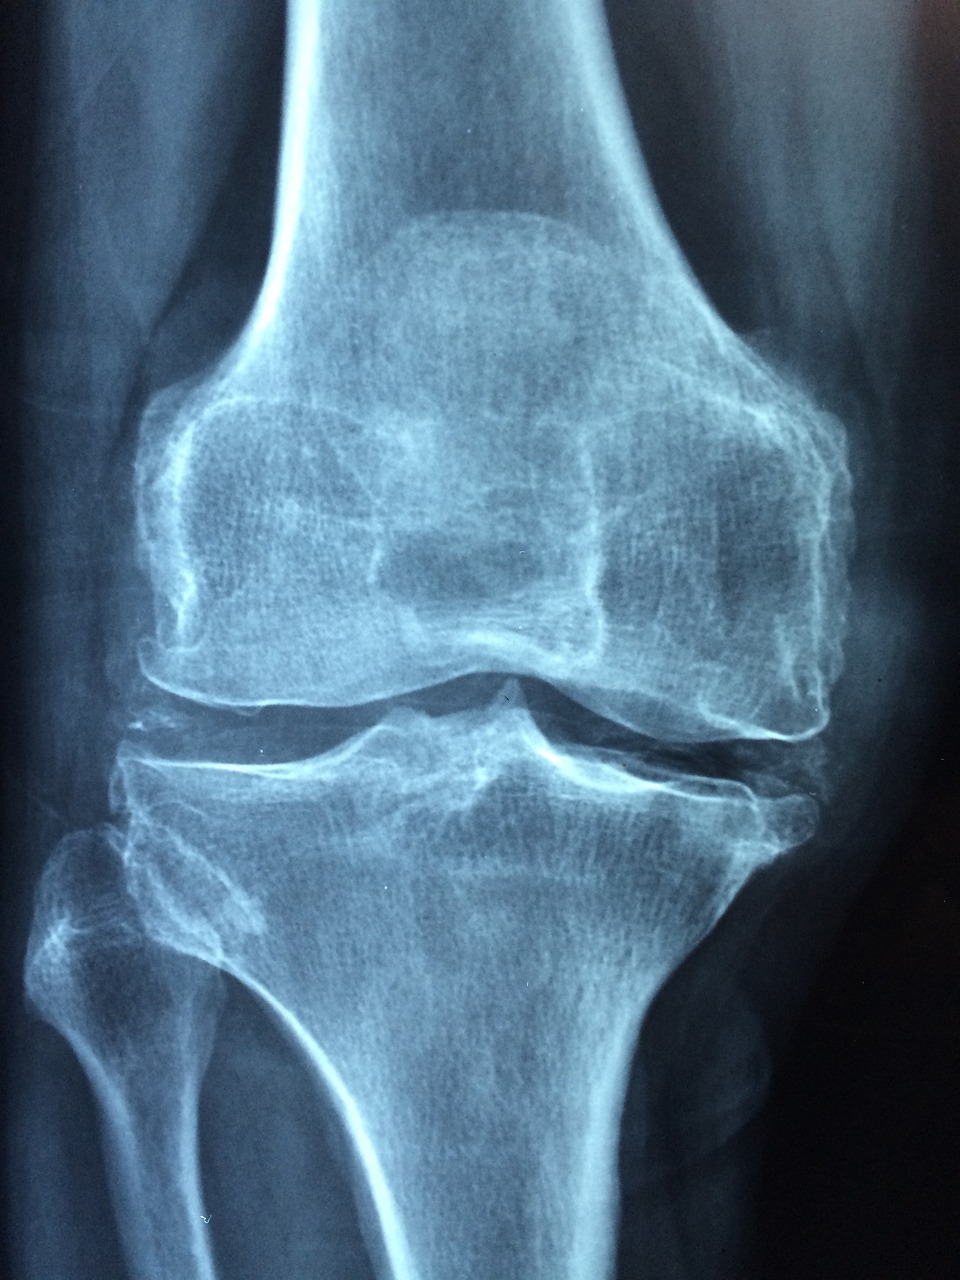

뼈의 강도가 약해져서 골절이 일어날 가능성이 높은 상태로 골다공이란 뼛속에 구멍이 많이 생긴다는 뜻이며, 골다공증은 뼈의 대표적인 미네랄인 칼슘과 인이 감소함에 따라 뼈의 양이 줄어들어 뼈가 얇아지고 약해져 잘 부러지는 질환을 의미합니다.

50~70세 여성의 골절은 주로 손목에서 먼저 발생하는 경우가 많으며 70대 환자들의 경우 고관절 및 척추의 골절이 흔하게 발생하게 됩니다.

골밀도는 주로 고관절 부위와 척추의 일부(허리뼈)에서 측정하여 가장 낮은 골밀도를 보이는 부위의 값을 기준으로 평가하게 되며 측정 결과는 T-값을 사용하는데 이는 ‘(환자의 측정값 - 젊은 집단의 평균값)/표준편차’로 골절에 대한 절대적인 위험도를 나타내기 위해 골량이 가장 높은 젊은 성인의 골밀도와 비교한 값이며, 값이 낮을수록 골밀도가 낮다는 것을 의미합니다.

T값이 -1.0 이상이면 정상이며, T-값이 -1.0에서 -2.5이면 골감소증, T-값이 -2.5이하면 골다공증으로 진단합니다.